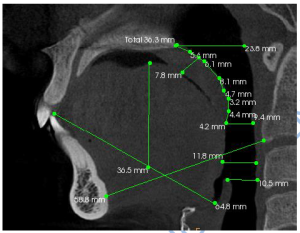

Her evaluation revealed:

- Mouth opening: 48 mm (adequate but painful)

- Bite: Well-aligned

- Muscle tenderness: Lateral pterygoid, masseter, temporalis

- MRI: Bilateral disc displacement without reduction

Instead of surgery, Aparna began customized orthotic therapy—a conservative, non-surgical approach designed for healing with care.